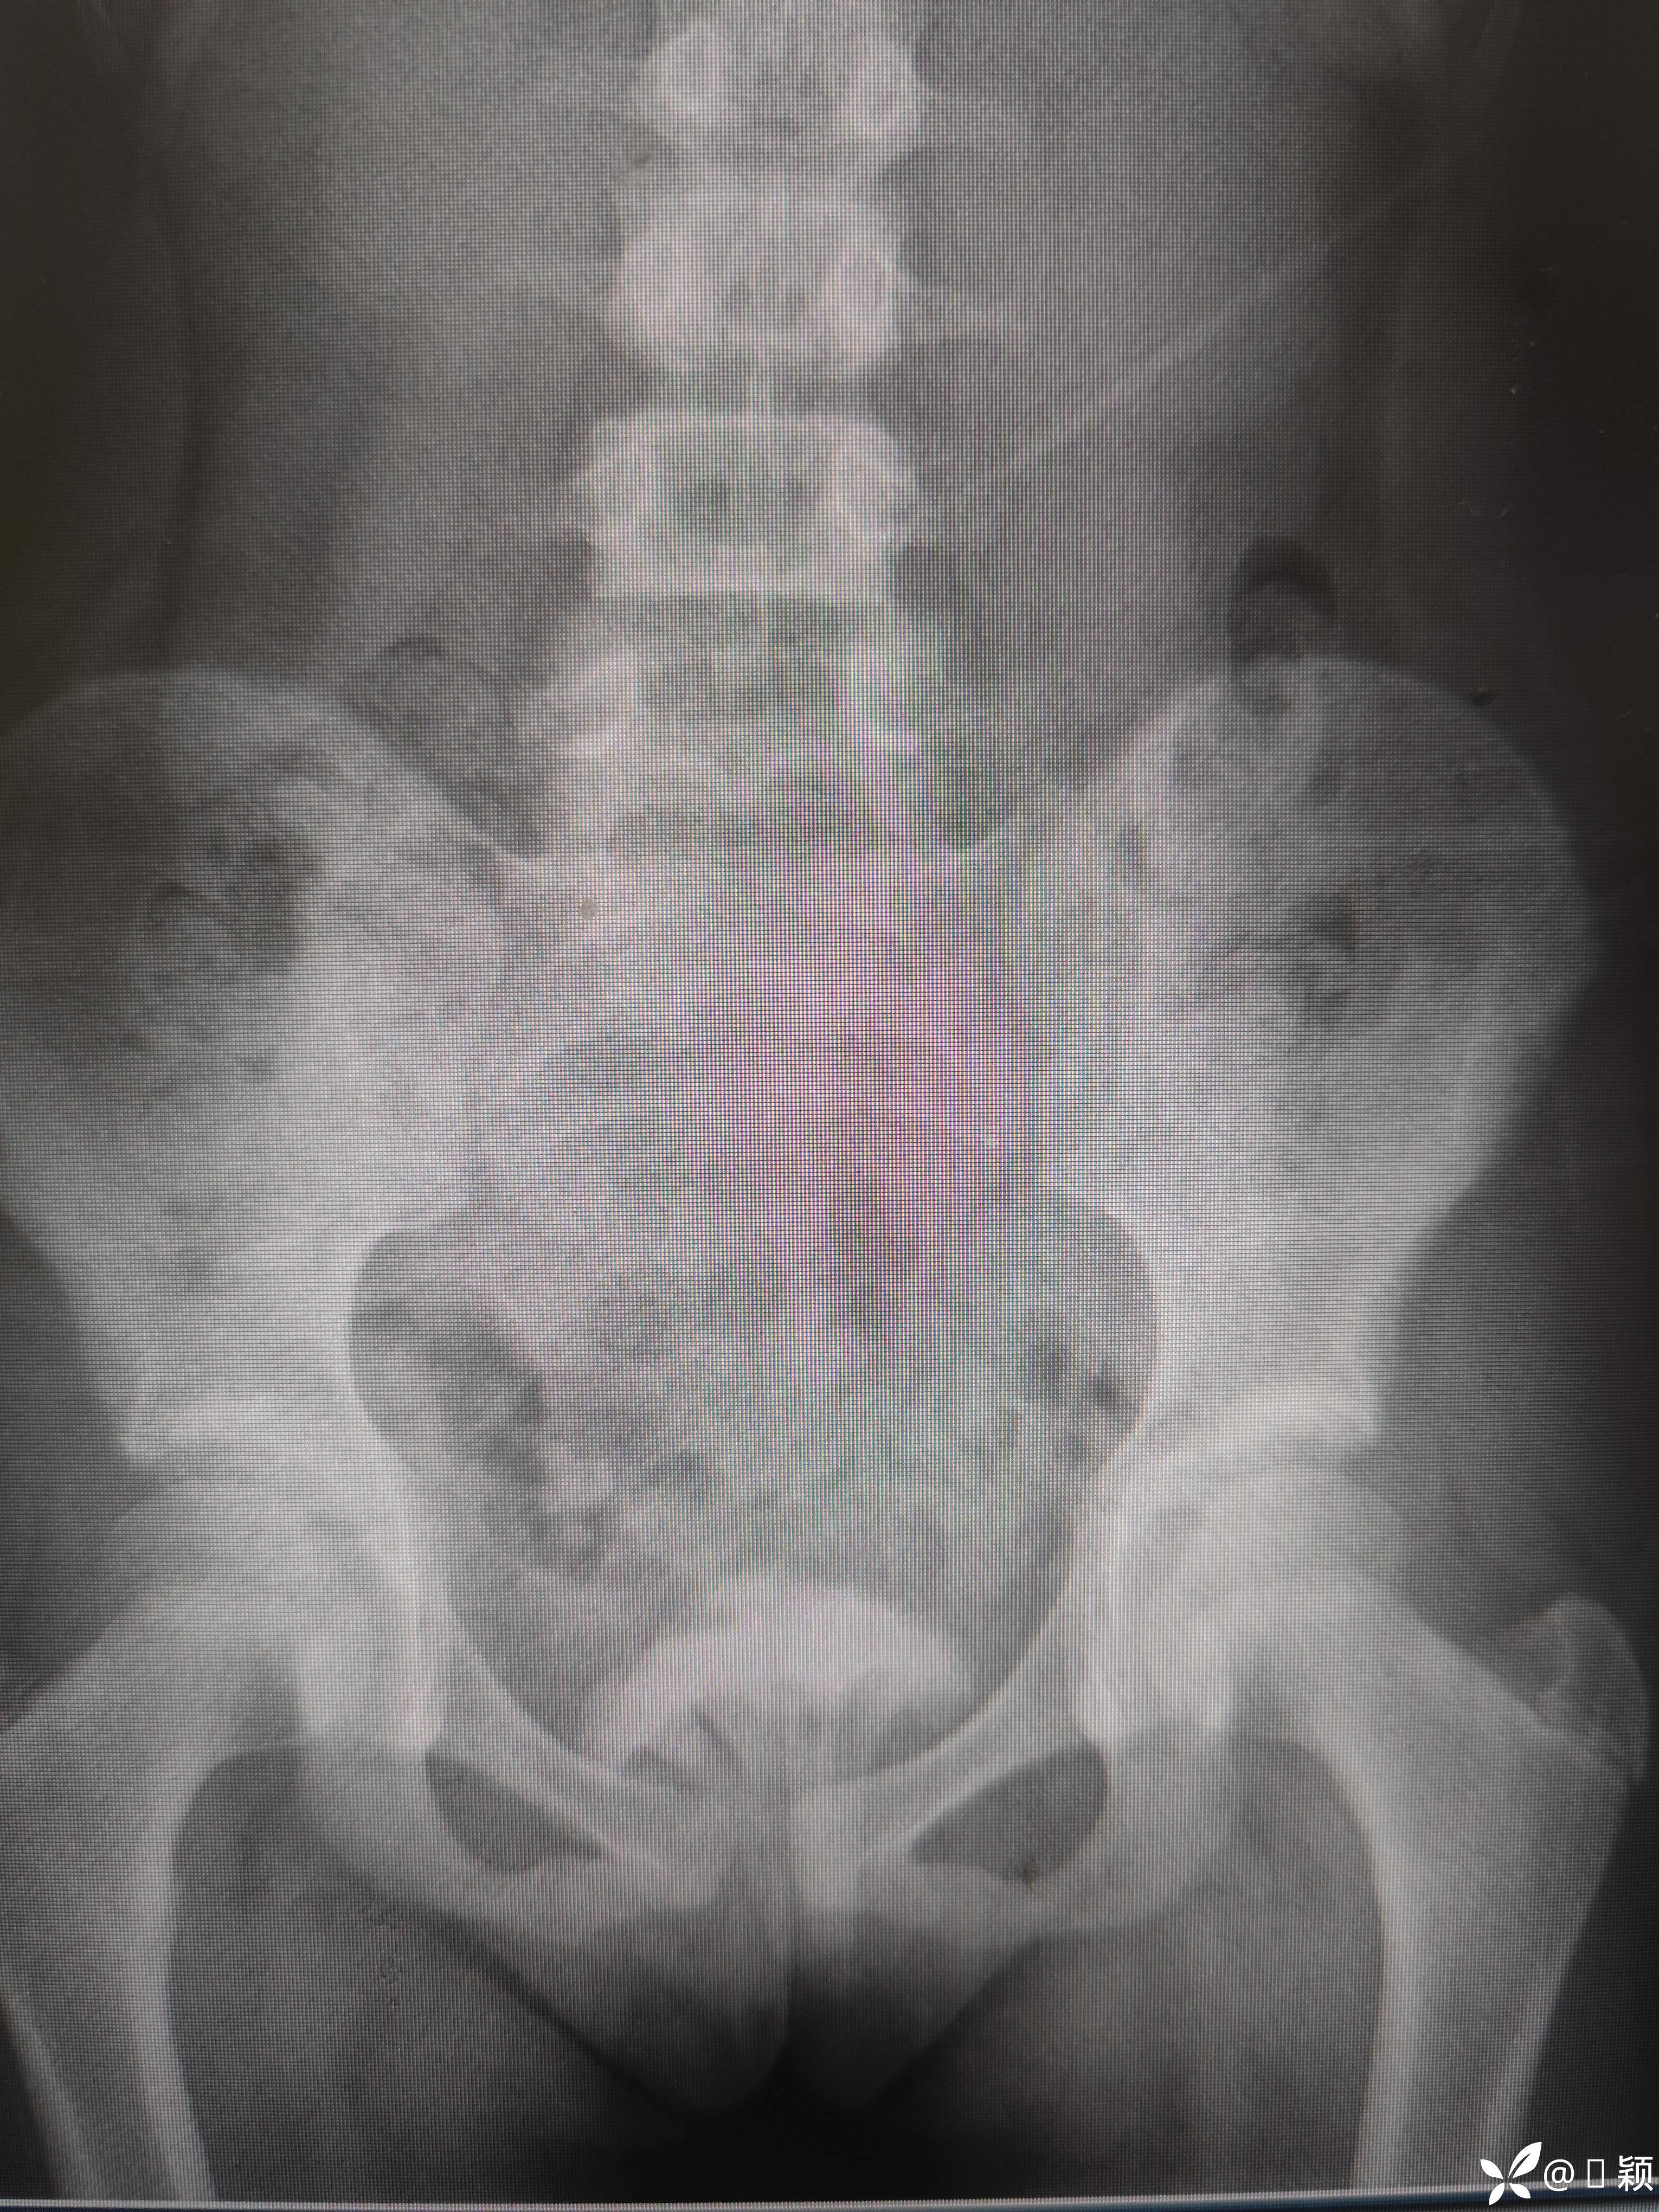

10岁女孩,留守,好奇把玩具“西兰花”塞进阴道,外阴未见损伤和血迹

请问各位同道、专家如何减少创伤把异物取出?